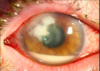

À ce moment, la tension intraoculaire augmente brusquement provoquant ainsi une crise de glaucome aigu. La tension intraoculaire peut monter jusqu’à 40 ou 50 mmHg, ce qui cause:

- une mydriase,

- des céphalées,

- des nausées et des vomissements.

Comment distinguer une uvéite aiguë d’une crise de glaucome aigu?

Il suffit simplement de regarder la pupille. Un oeil en uvéite aiguë est un oeil douloureux et rouge habituellement en miosis.

Par contre, un oeil en glaucome aigu est un oeil rouge et douloureux en mydriase.

Pourquoi une crise de glaucome aigu cause un oedème de la cornée?

La surface interne de la cornée est tapissée d’une couche de cellules dites endothéliales. La responsabilité de ces cellules endothéliales est de pomper l’humeur aqueuse de la cornée vers la chambre antérieure pour maintenir la clarté de la cornée.

Certains auteurs ont fait l’analogie entre la cornée à un bateau avec une fuite chronique et des cellules endothéliales qui travaillent en quelque sorte comme une pompe pour vider la cornée de l’humeur aqueuse.

Dans le contexte d’une crise de glaucome aigu, la tension très élevée dans la chambre antérieure force une grande quantité d’humeur aqueuse vers la cornée. Les cellules endothéliales sont incapables de compenser pour l’influx massif d’humeur aqueuse et la cornée va alors enfler, créant un épaississement de la cornée (oedème cornéen).

La cornée devient grise de façon diffuse et les patients se plaignent de halo autour des lumières qui sont causés par une diffraction de la lumière à travers les cellules cornéennes oedématiées.